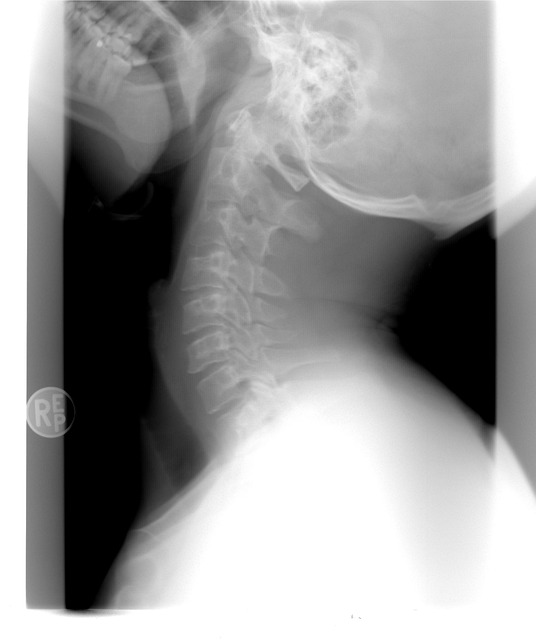

🦴 4. 관절 통증 & 근육 약화

→ 에스트로겐이 뼈 건강에도 관여하는 호르몬이라서,

갱년기엔 골다공증, 손목통증, 무릎 시큰거림도 종종 나타나요.